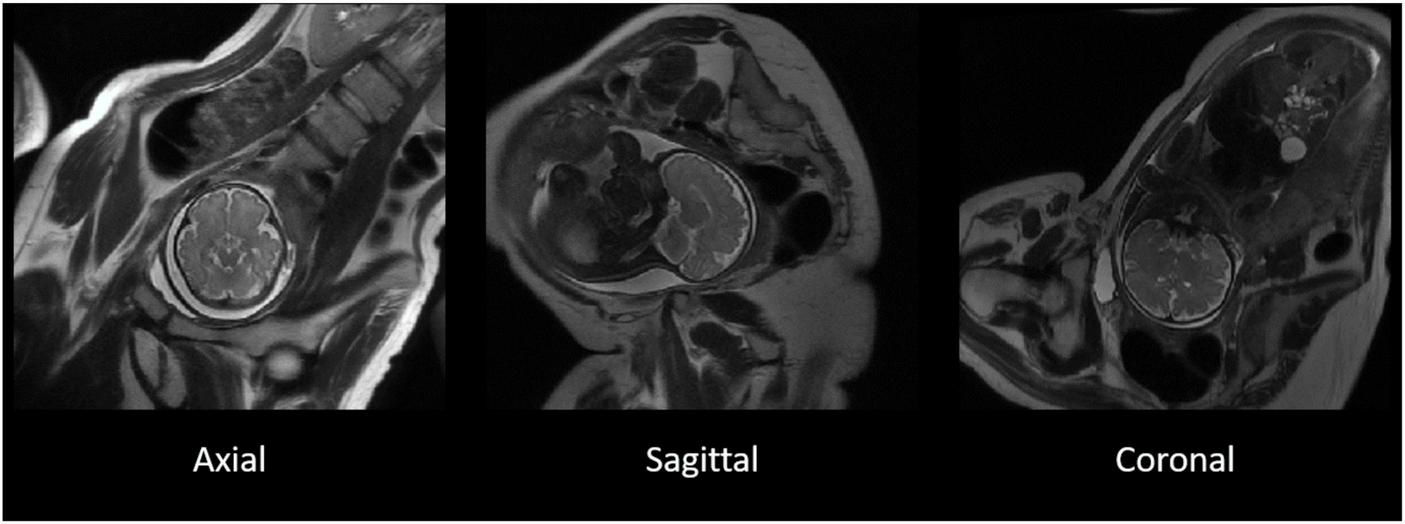

The T2-weighted MR images were acquired using a single shot fast spin echo (SSFSE) sequence [repetition time (TR) > 1,200 ms, echo time (TE): 81.36–93.60 ms, voxel size: 0.98 mm × 1.96 mm × 8 mm and 0.125 mm × 0.17 mm × 9 mm], applied in three image planes (Figure 1).

FIGURE 1

The original T2-weighted acquisition of a fetal MR image in axial, sagittal, and coronal planes. T2-weighted images acquired separately in three separate image planes in the axial (left), sagittal (middle), and coronal (right) in a representative participant. The three image planes were subsequently used for the reconstruction of 3D images.